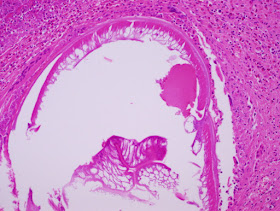

The following was seen in resected periumbilical skin nodule from a 60 year old male.

(20x original magnification, H&E)